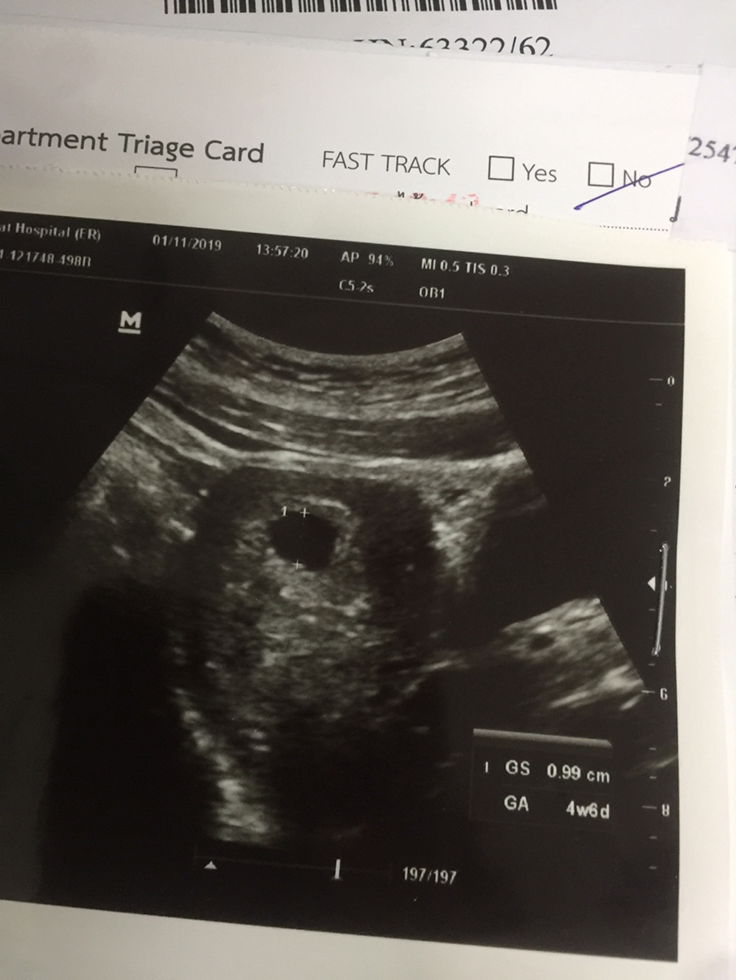

รูปแรกวันที่1 รูปสองวันที่4 รูปสามวันที่11

เมื่อวันที่1พฤศจิกายนมีเลือดออกไปห้องฉุกเฉินซาวไม่เจอเด็กหมอให้กลับบ้าน วันที่4พฤศจิกายนไปอีกหมอซาวช่องคลอดเจอไข่แดงแล้วยังมีเลือดออกอยู่สีน้ำตาล วันที่10พฤศจิกายนมีเลือดออกปวดท้อง วันนี้11พฤจิกายนไปหาหมอเพราะมีออกมาอีกแถมปวดท้องหมอไปซาวทางช่องคลอดถุงใหญ่ขึ้นแต่เจอถุงไข่แดงแต่เห็นน้องไม่ชัดหมอบอก50/50อาจจะแท้งหรือไม่แท้ง อาจจะท้องลมด้วย คือหมอพูดงงมากเลยคะฟัง3คนยัง ไม่มีใครรู้เรื่องเลย ไม่ให้ยากันแท้งไม่ฉีดไม่ทำอะไรเลยนอกจากซาว แล้วบอก50/50เรามีเลือดตั้งแต่วันที่1ไม่ได้รับการรักษาอะไรเลยจนตอนนี้วันที่11แล้วก็ยังโดนไล่กลับบ้าน?6วีคมีใครยังไม่เจอน้องไหมคะหมอบอกมีไข่แดงแต่ยังไม่ชัด

คือตอนนี้ประมาณ11วีคแล้วคะแต่ไปห้องฉุกเฉินเพราะมีเลือดออกหมอซาวให้(ครั้งแรก)ในห้องฉุกเฉินหมอก็พูดออกมาว่าท้องลมไม่เจอเด็กแล้วให้เรากลับบ้านเครียดอยู่4วันหมอนัดอีกไปอีกหมอไปซาวอีกครั้งที่ห้องซาวผลปรากฏว่าเจอน้องแต่น้องตัวเล็กคุณแม่ดีใจจนอยากจะก้มลงไปกราบคุณหมอที่หาน้องจนเจอ คือเราก็เริ่มหมดหวังเพราะใบซาวที่หมอบอกท้องลมมัน4วีคแต่ความจริงเรา11วีคเรานึกว่าถุงตั้งครรภ์น้องไม่โตพูดง่ายๆหมดหวังไปแล้ว สรุปมาวันนี้หมอเจอน้องแล้วคะแต่น้องเล็กมากๆแต่หมอยังไม่ได้บอกเลยว่าได้ยินเสียงหัวใจไหมแต่เห็นว่ามีน้อง?❤️อยากให้เรืองนี้เป็นประโยชน์ต่อแม่ๆที่กังวลที่หาน้องไม่เจอให้เวลาน้องหน่อยนะคะอย่าพึ่งท้อแบบเราหมั่นดูแลสุขภาพขอให้เจอน้องขอให้น้องสู้แบบเรานะคะ?

คือเราตรวจเจอว่าท้องตั้งนานแล้วคะจนตอนนี้ประมาณ2เดือนได้แล้วคะแต่ไปห้องฉุกเฉินหมอซาวบอกไม่เจอเด็กพอมานัดวันนี้หมอเอาใบซาวมาให้แต่ปรากฏว่าในใบซาวมัน4วีคเองคะมันดูจากตรงGAใช่ไหมคะคืองงว่าแล้วที่ตรวจเจอมาตั้งนานนั่นคืออะไรงงมากๆเลยคะตอนนี้หมอบอกไม่เจอเด็กตอนที่เราบอกว่าประมาณ11วีคในห้องฉุกเฉินคือเราเครียดร้องไห้มาหลายคืนเพราะคิดว่าน้อง11วีคต้องเห็นแล้วแต่หมอไม่พูดอะไรแค่บอกว่าไม่เห็นพอมาวันนี้เอามาให้แต่บอก4วีคคือมันยังไงคะ